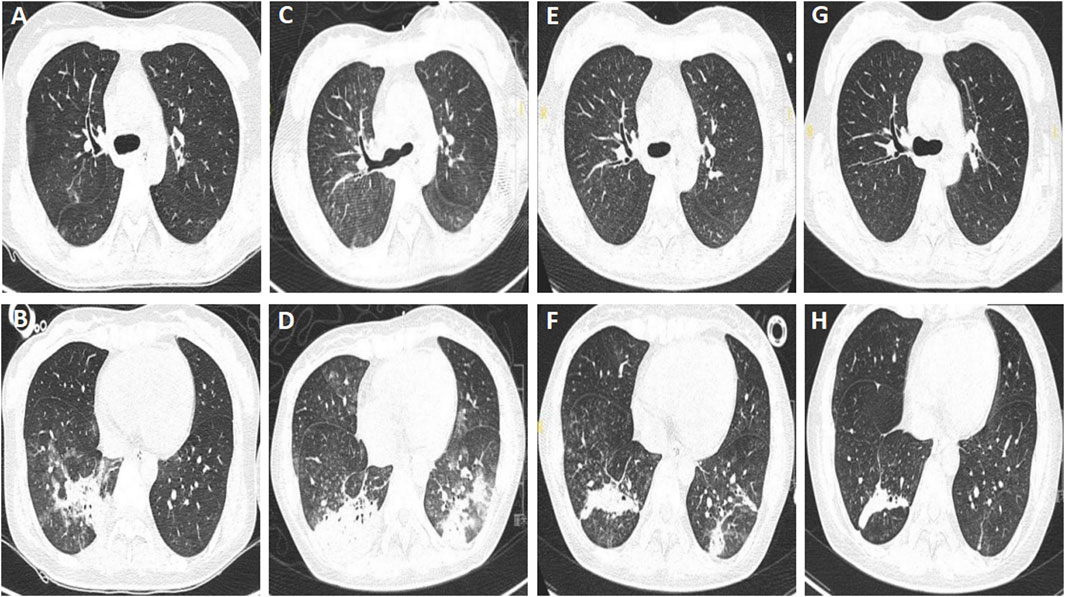

The patient’s vital signs were normal on admission, except for that the muscle strength of both lower limbs were grade 4/5. Laboratory examination revealed leukocytosis (14.04 × 109/L) and hypo-potassium (3.13 mmol/L), while other parameters were with normal range. The chest computed tomography (CT) taken on May 19th showed multiple patchy ground-glass opacities and consolidations with ill-defined borders in both lungs, which was consistent with aspiration pneumonia (Figures 1A,B). The patient received treatment with neostigmine, mecobalamin and vitamin B1 to improve the symptoms. She didn’t receive botulinum antitoxin injection due to the strongly positive skin test. Piperacillin tazobactam was administered to control the pneumonia at a dose of 4.5 g, every 8 h. The patient was successfully weaned from the ventilator on 26 May 2021. However, she got a fever of 38.8 °C, and productive cough with yellow phlegm on May 30th, so noninvasive ventilation was applied. Her dyspnea persisted and the partial pressure of arterial carbon dioxide (PaCO2) increased to 54 mmHg, therefore she received tracheostomy and mechanical ventilation on June 1st. This decision was made according to the recommendations for adult tracheostomy (Nelson et al., 2010; Lee et al., 2024). On June 2nd, the chest CT showed that the infiltrating fields increased (Figures 1C,D), and carbapenem-resistant Enterobacter cloacae and Acinetobacter baumannii were cultured from sputum specimens, then amikacin at a dose of 400 mg every 12 h was used to replace piperacillin tazobactam as per culture susceptibility test. The patient’s condition improved and she was weaned from the ventilator and received oxygen therapy at a concentration of 35% on June 8th, while the antibiotics was stopped on the same day. Chest CT were taken on June 11th, and June 20th, respectively, and the results showed that the pulmonary infection were absorbed gradually (Figures 1E–H). The tracheostomy tube was removed on June 24th, and the patient discharged with slight dysphagia left on 1 July 2021.

Figure 1. Chest computed tomography of patient A. (A,B) Multiple patchy ground-glass opacities and consolidations with ill-defined borders in both lungs, taken on 19 May 2021. (C,D) Increased infiltrating areas, taken on 2 June 2021. (E–H) Infiltrating areas absorbed gradually, taken on June 11th, and 20 June 2021, respectively.